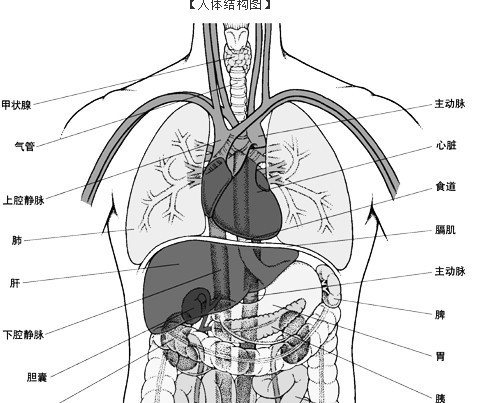

肺在人体的哪个位置图

肺在哪个部位?它是干什么的?

发生在肺内的气体交换,第三章人体的呼吸,,肺的位置,,,位于胸腔内

人体的肺在哪个部位?求图片